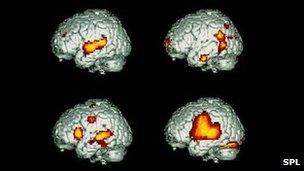

The team focused on an area of the brain called the superior temporal gyrus, or STG.

This broad region is not just part of the hearing apparatus but one of the "higher-order" brain regions that help us make linguistic sense of the sounds we hear.

To do that, the team employed a computer model that helped map out which parts of the brain were firing at what rate, when different frequencies of sound were played.

The technique hinges on plotting brain activity across a number of frequencies